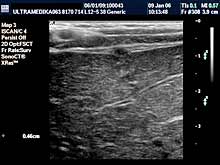

- Dojke

Pregled dojki može biti indikovan ako dolazi do naglog uvećanje

dojke ili do pojave izraštaja koji se pipa. Ultrazvučni pregled je

sigurno prva dijagnostička procedura, jer je Sono CT tehnika u

prednosti kod otkrivanja malih promena uodnosu na mamografiju, zbog

veće preciznosti, a pri tome je izbegnuto i jonizujuće zračenje.